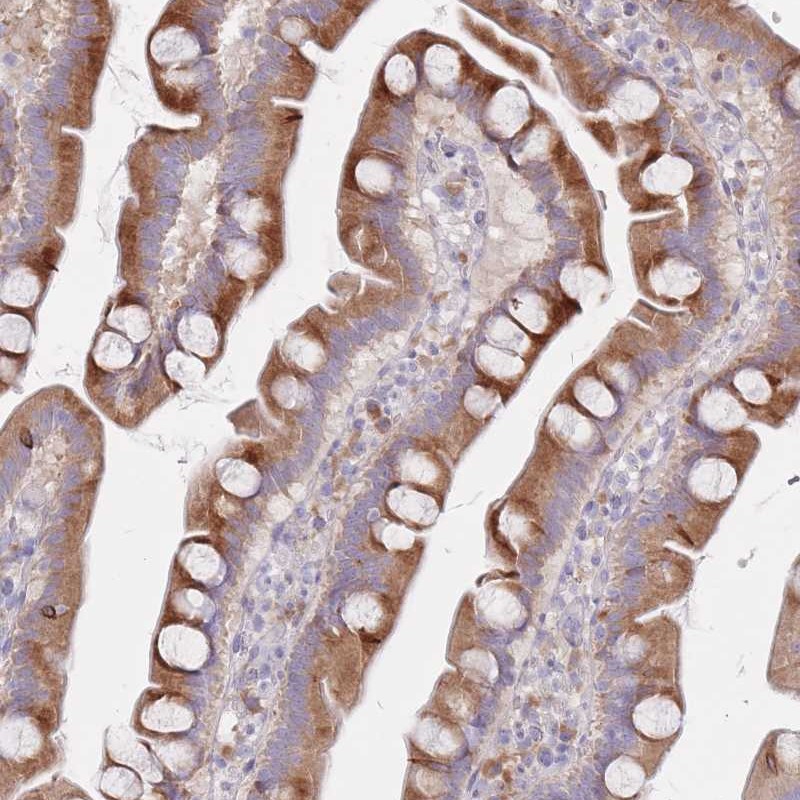

Immunohistochemical staining of human small intestine shows strong cytoplasmic positivity in glandular cells.